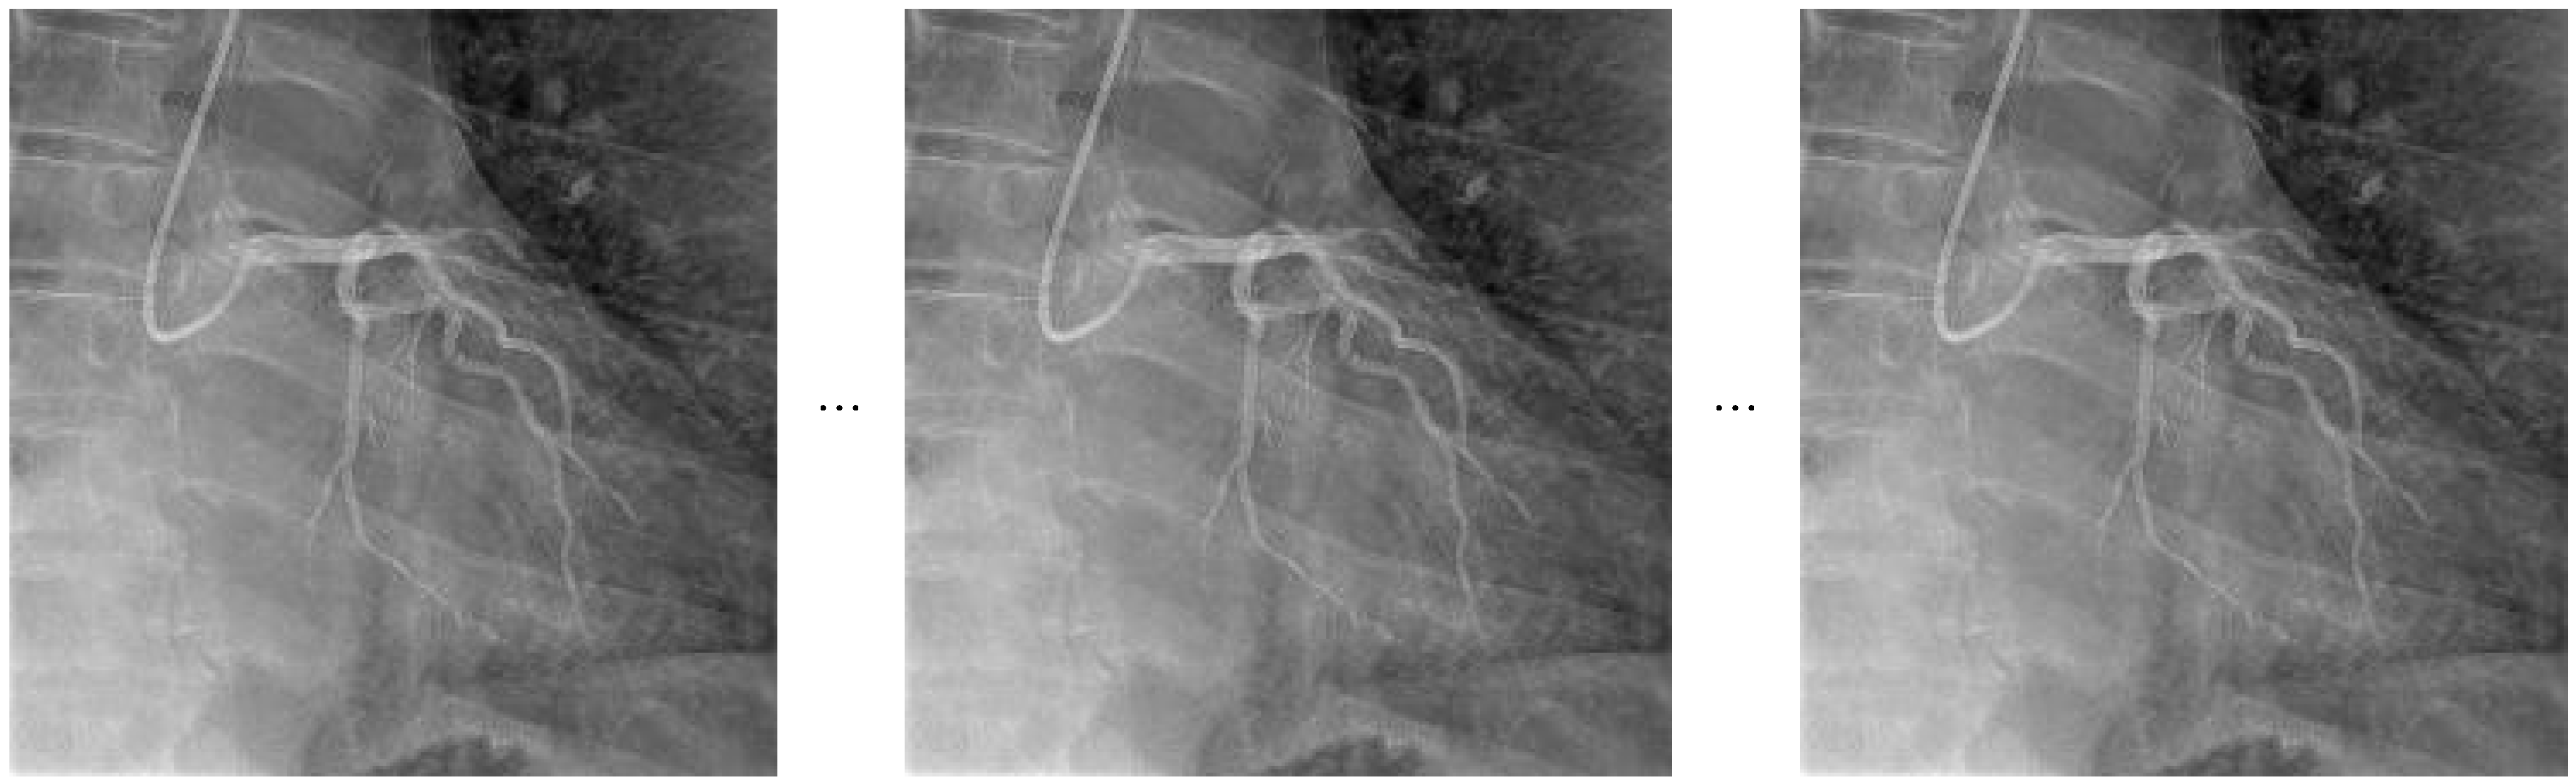

The general architecture of the Temporal Segment Networks (TSNs) used in this study is illustrated in Figure 1. The diagram depicts the input video sequences being divided into temporal segments, from which sparse frames are sampled. These sampled frames are individually processed by Convolutional Neural Networks (CNNs), and the final class predictions are subsequently generated through a segmental consensus mechanism that aggregates the individual segment outputs.

The temporal sampling strategy adopted within the TSN architecture involves dividing each video sequence into evenly spaced segments and selecting representative frames from each segment. A visual illustration of this approach is provided in Figure 2.